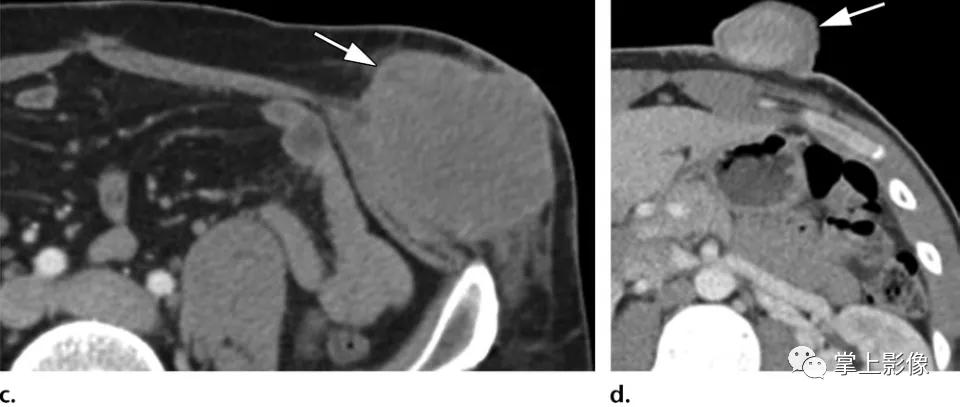

6例不同患者腹壁肉瘤的不同表现。比较可触及的腹壁肿块(a-c)和浅表溃疡性肿块(d-f)的表现。(A)一名38岁男性的轴位CT影像显示,皮下脂肪(经检查认为是腹股沟疝)有一边界清楚的小上皮样肉瘤(箭头)。(B)一名33岁男子的轴位CT影像显示,腹部下方肌肉深处平滑肌肉瘤(箭头)(病人右大腿亦有肿瘤[未显示])。(C)21岁男性轴位CT影像显示横纹肌肉瘤(箭头),患者的左大腿也有肿瘤(未显示)。(D)一名24岁男性的轴位CT影像显示一浅表性隆起性皮肤纤维肉瘤(箭头),影像上并无严重溃疡,但体格检查显示皮肤水肿及出血。(E)71岁女性的轴位CT影像显示浅表上皮样血管肉瘤(箭头),表现为溃疡性伤口。(F)一位62岁女性的轴位CT影像显示一深部浸润性滑膜肉瘤(箭头),表现为溃疡性伤口。所有诊断均经手术切除或活检证实